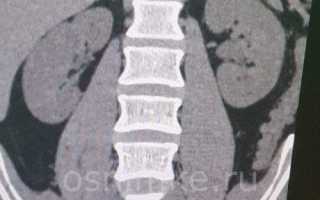

КТ почек с контрастом. Источник: infomrt.ru